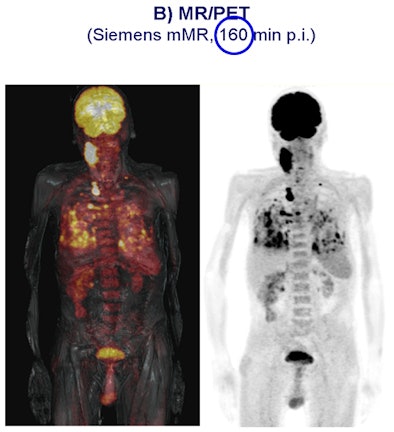

In a German study, 11 patients with cancer underwent single-injection PET/CT followed by PET/MRI (Biograph mMR, Siemens Healthcare). Simultaneous PET/MRI acquisition was feasible and offered good-quality PET and MRI diagnostic data.

The analysis found that all 13 lesions detected at PET/CT were also identified by PET/MRI, with no significant difference between PET/CT and PET/MRI regarding the uptake ratios.

The study "demonstrates for the first time that newly introduced integrated whole-body MR/PET technology allows simultaneous acquisition of high-quality MR and PET data in a clinical setting within an acceptable time frame," wrote lead study author Dr. Alexander Drzezga from TU München.

| Carcinoma is compared in a patient who received a PET/CT scan 80 minutes after contrast injection (above), followed by a PET/MRI scan 160 minutes after contrast injection (below). All images courtesy of SNM. |